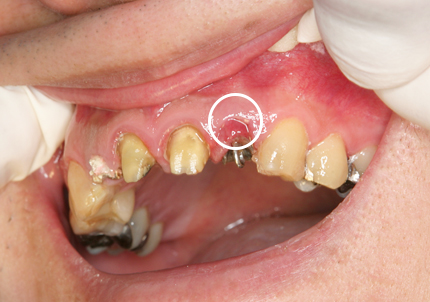

患者:Y.S 様

初診日 :2018年10月

主訴 :上顎前歯部審美障害、臼歯部補綴治療

1.初診時口腔内写真(2018年10月)